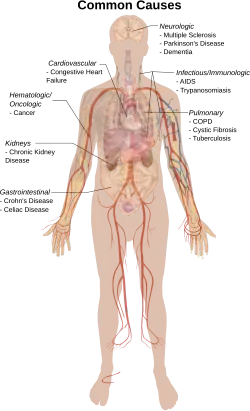

Other conditions that frequently cause cachexia include:

Cachexia can happen in late stages of diseases like cystic fibrosis, multiple sclerosis, motor neuron disease, Parkinson's disease, dementia, tuberculosis, multiple system atrophy, mercury poisoning, Crohn's disease, trypanosomiasis, rheumatoid arthritis, celiac disease, and other diseases that affect the entire body.[15][16]